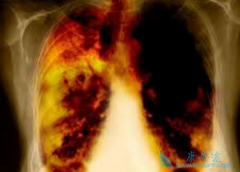

过去对于肺癌的治疗大方向就是手术、化疗以及放疗三大经典手段,经过近十几年的研究,在非小细胞肺癌里面针对有驱动基因表达的患者,又增加了小分子靶向药物的治疗;另外,近几年免疫治疗也开始在临床上推行。现在肺癌治疗已经进入精准医学时代,以靶向 ...

从肿瘤内科来看,临床上大约80%-80%的肺癌患者处于晚期,对于早期肺癌,单纯采用手术治疗即可,肺癌中期,除了手术治疗外,还需辅助放化疗,晚期肺癌患者主要以内科治疗为主,包括化疗、靶向治疗以及姑息性的放疗等手段。 厄洛替尼 (ERLOTINIB)作为二 ...